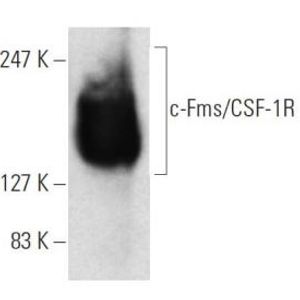

APR 22, 2016Health & MedicineMacrophages exist in every type of body tissue, in the lungs as alveolar macrophages and in the liver as Kupffer cells. ...